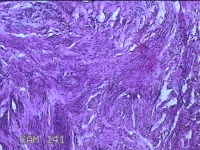

宫颈组织

性别

女

年龄

44岁

临床诊断

宫颈赘生物

一般病史

发现宫颈赘生物2年余。

标本名称

大体所见

灰白暗红色组织3.8x1.5x0.8cm一块,表面光滑,以宫颈12点缝线标记处切开,切面灰白粉红色,质软,宫颈3点处见灰白粉红色囊性肿物1.8x1.5x0.3cm一个,切开肿物,内见大量乳白色内容物,囊壁厚0.1cm。